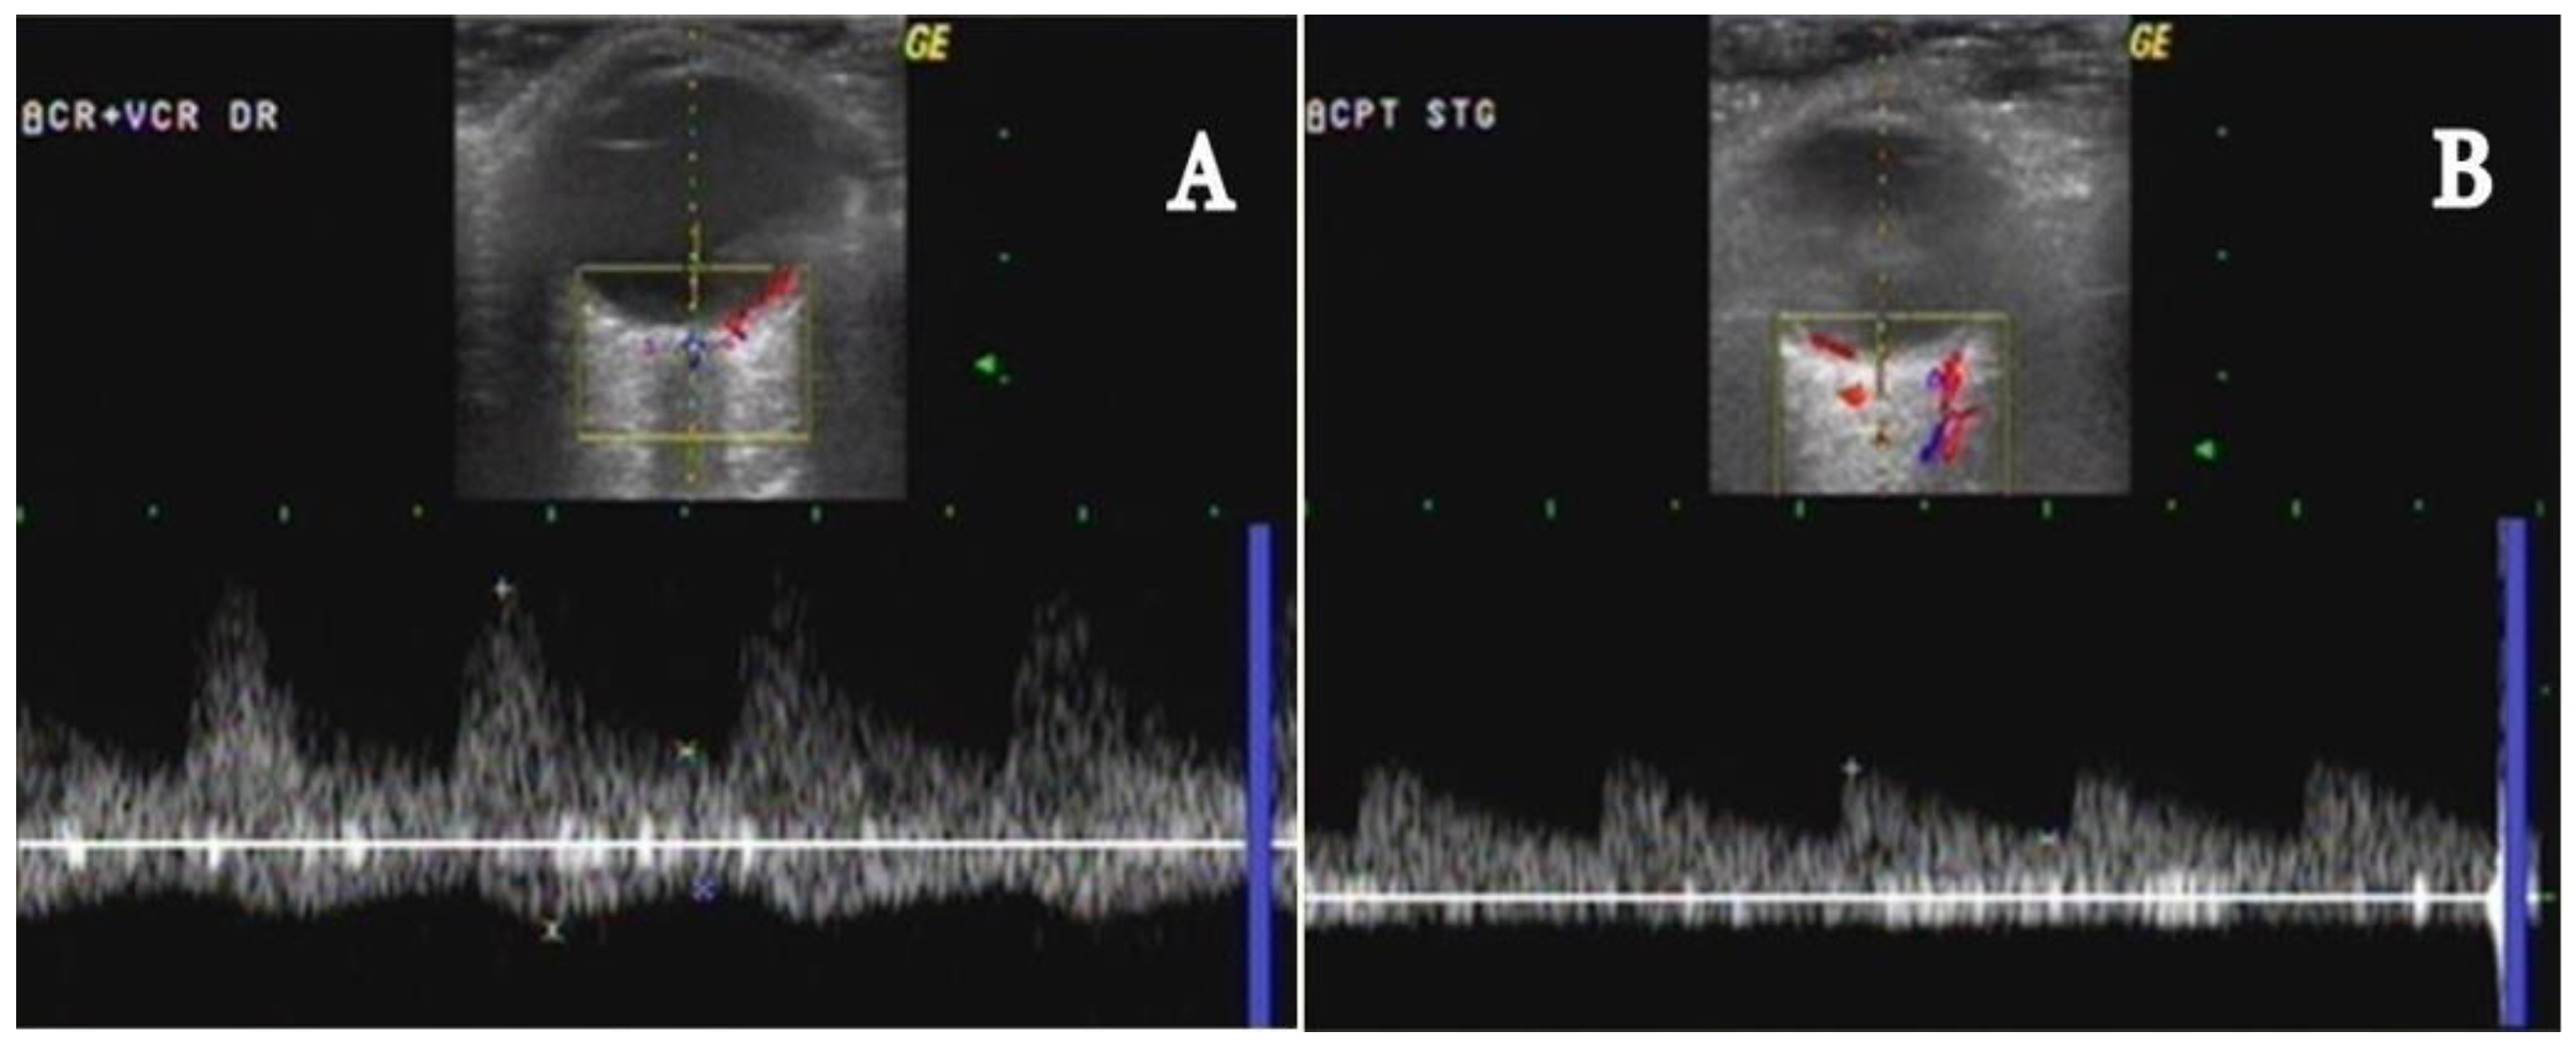

- Stenoses are characterized by aliasing and persistent diastolic flow by colour Doppler US. The peak systolic velocity (PSV) assessed within the stenosis area by pulsed-wave Doppler US is two or more times greater than the PSV recorded in the prestenotic segment of the vessel, with turbulence at the level of stenosis, associated with diminished velocities distal to the stenosis [30,31,32,33,34,35,36,37,38,39,40,41] (Figure 3) [11].

- Acute occlusions, wherein the US image is similar to that of acute embolism in different other vessels, with lack of color Doppler signals (even with low pulse repetition frequency and high color gain) in a visible artery lumen filled with hypoechoic material (cloth) [30,31,32,33,34,35,36,37,38,39,40,41].